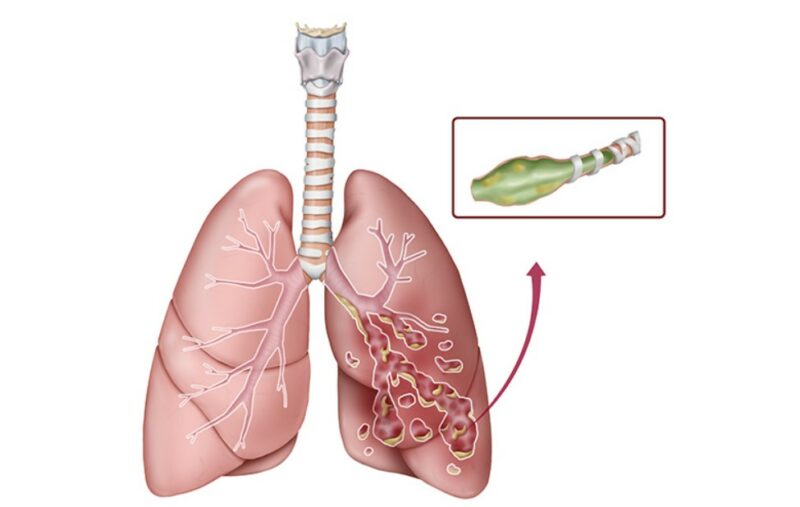

Bronşektazi, akciğerde yer alan hava yollarının kalıcı bir şekilde genişlemesidir. Verem, Zatürre gibi geçirilmiş hastalıklardan veya Kistik Fibrozis gibi doğuştan gelen rahatsızlıktan kaynaklanabilir. En sık görülen belirtileri öksürük, rahat nefes alamama ve sık akciğer enfeksiyonu gelişmesidir. Yaşam süresini etkilemez.

Bronşektazi enfeksiyon ve inflamasyon sonrasında akciğerde yer alan hava yollarının genişlemesi sonrasında görülür. Ayrıca bu sırada görevi mukusları temizlemek olan silyalar hasar görür. Genişlemiş alanlarda mukus birikmeye başlar. Biriken mukusu atmak için devreye öksürük girer. Çok şiddetli ve uzun süreli öksürme sonrasında akciğerlerde olan küçük damarlar hasar görebilir. Bunun sonucunda kanlı balgam gözlenir.